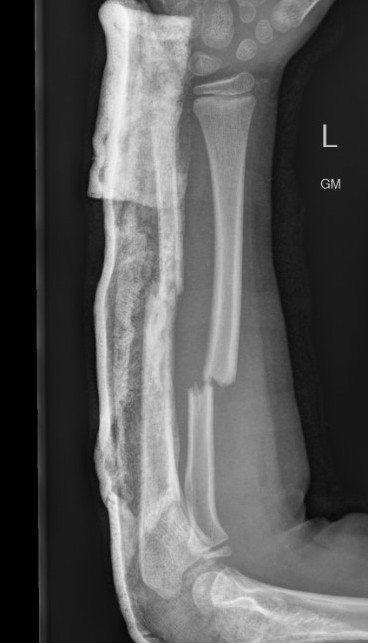

Nonunion

Fernandez et al J Paediatr Orthop 2009

- 592 patients treated with elastic nail

- 6/592 (1%) nonunion / pseudoarthrosis

- all in ulna, 5/6 opened in surgery to facilitate nail passage

Refracture

Makki et al J Paediatr Orthop B 2014

- plate removal refracture rate 8.5% if removed within 12 months of implantation

- nail removal refracture rate 17% if nail removed within 6 months of implantation

- 82 children with retained forearm plates followed for 8 years

- 7% incidence of implant related fractures